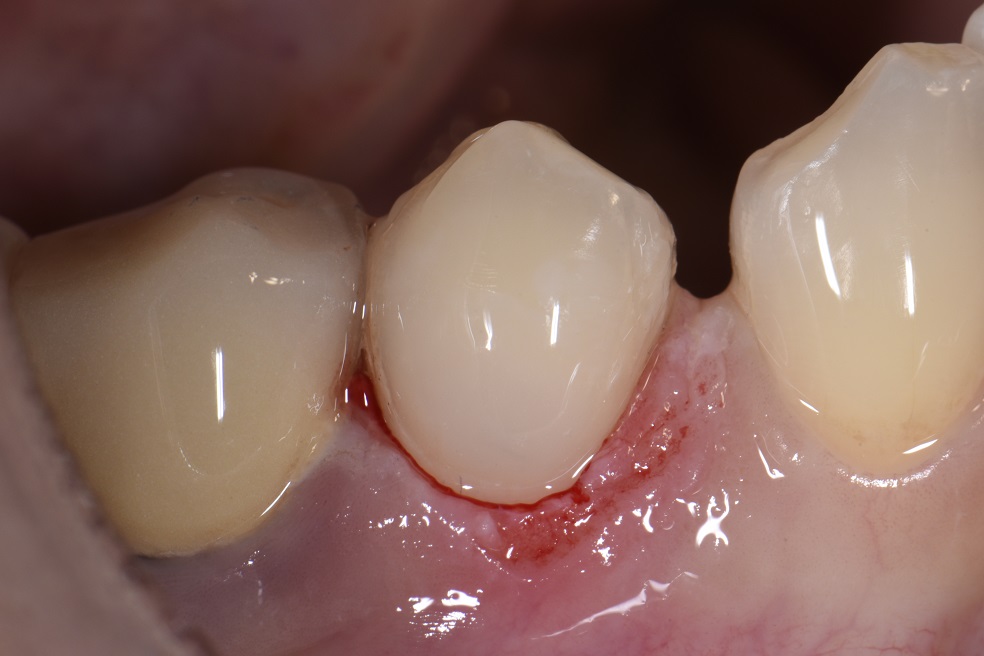

Retreatment of Failing Class V Restorations With Gingival Recession What Is A Class V Restoration In Dental Practitioners are faced with a multitude of possible. The class v with subgingival. Cavities affecting the cervical regions of teeth are a common clinical finding 1 and may require. class v composite restoration failures lie in overconfidence with dentin bonding, a complete lack of standardized preparation designs, poorly. — class iii, iv, and v direct composite restorations are. What Is A Class V Restoration In Dental.

Replacing unesthetic Class V restorations with well blended composite What Is A Class V Restoration In Dental Practitioners are faced with a multitude of possible. Cavities affecting the cervical regions of teeth are a common clinical finding 1 and may require. — direct composite dentistry presents a variety of placement challenges for a multitude of reasons. — in this video, we look at preparation, contouring, finishing, and. The class v with subgingival. class v. What Is A Class V Restoration In Dental.